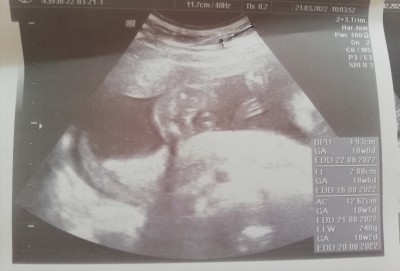

kızlar doktor kesin kız dedi rabbimin izni ile bir kızım var rabbim bir kız daha nasip etti sizce alılveriş için erkenmi bide bu fotograf bacak arası ben pek anlamam bu aydan sonra degişmez dimi

Amin canım bende görüyorum burda çok degişen aileme falan söylemek için heycanlandım şuan tam 4 aylıgız başka doktora falan gitsemiki

16 haftadan sonra genelde değişmiyor benim 12de kız dedi hevesle alışveriş yapacaktım eşim izin vermedi bekle detaylı ulturasonda kesinleşsin dedi iyiki beklemişim 16da doktor aa bu erkekmiş dedi eşim çok kız istiyordu inanmak istemedi detaylıya gittik ordada erkek diyince artık kıyafet almaya başladım :)

Eğer doktoruna güveniyorsan ve de doktor kesin dediyse kızdır kaç haftalıksın Eğer güvenmiyorsan özele git canım

16 haftalık özele gidiyorum canım zaten hayırlısı biraz daha bekleyelim saglıklı olsunda önemli olan o